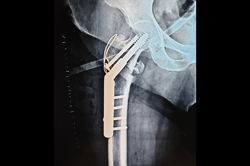

Intertrochanteric Fracture